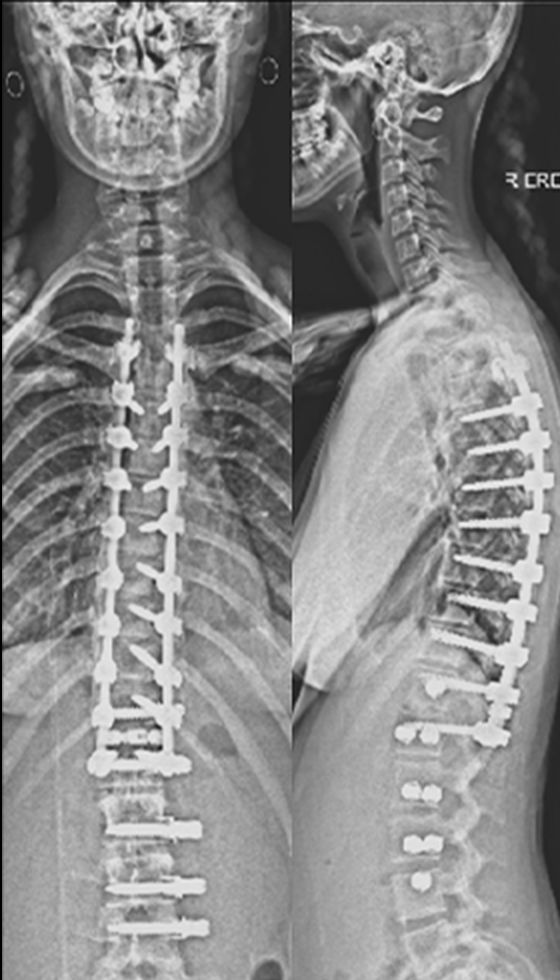

Gallery : Before - After